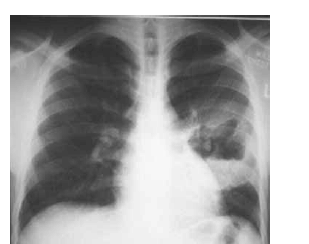

Um menino de quatro anos de idade, morador de uma instituição de apoio a menores abandonados, foi levado a uma emergência pediátrica com história de febre alta havia três dias. Nesse período, o quadro clínico evoluiu para dificuldade respiratória e gemência. No exame físico da criança, foram constatados, além de febre e dificuldade respiratória, palidez, aspecto toxêmico, sinais de desidratação e uma lesão pustulosa tensa no membro inferior direito. A radiografia de tórax do paciente apresentou o seguinte aspecto.

Nesse caso, a criança deverá receber tratamento específico à base de oxacilina.

Um lactente de um mês de idade, nascido de parto vaginal, apresentava tosse seca havia uma semana. O exame físico do bebê constatou temperatura axilar de 37 ºC, hiperemia, edema e secreção serosa em conjuntivas, leve taquipneia e murmúrio vesicular rude com creptações disseminadas à ausculta pulmonar. Foi realizada radiografia do tórax, conforme ilustrado a seguir.

Nesse caso, o diagnóstico mais provável é pneumonia por Chlamydia trachomatis, e o tratamento do paciente deve ser realizado com azitromicina, na dose de 30 mg/kg por cinco dias.